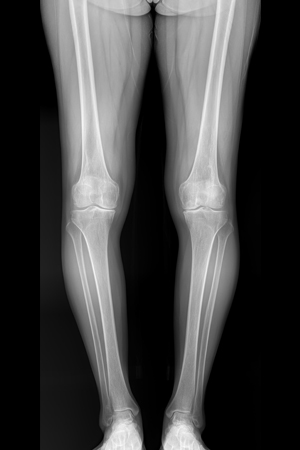

로봇인공관절 수술은 의사의 수술 노하우와 로봇의 정확성이 결합된 최첨단 무릎 인공관절 수술입니다. 수술 전 CT 검사 후 로봇이 검사 결과를 3D 화하여 환자의 무릎 상태를 정확히 파악한 후, 세밀한 수술 계획을 제안합니다. 그리고 의사가 로봇암(Robot Arm)을 잡고 정밀하게 뼈를 절삭한 후 최적의 인공관절을 삽입하는 수술 방법입니다. 컴퓨터 프로그램으로 환자의 무릎 상태를 정확히 파악한 후 로봇수술 집도 인증을 받은 정형외과 전문의가 집도하므로 수술의 위험도가 적고 연부 조직의 손상을 최소화할 수 있는 장점이 있습니다.

CT 단층촬영,

X-Ray 검사